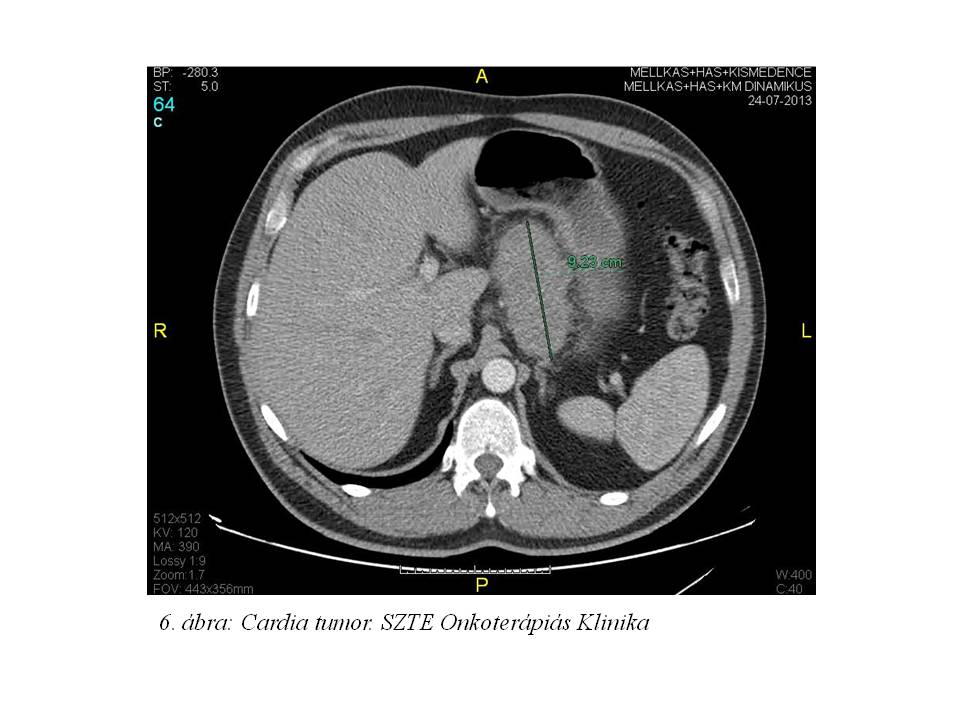

44 éves férfibetegünknél 2013 nyarán fokozódó nyelési panaszok miatt indult kivizsgálása nyelési panaszok és bőrelváltozások miatt. Bőrelváltozásai mindkét oldalon az axillákra, és az inguinakra kiterjedtek, borsnyi, borsónyi veruccosus formában. A bőrgyógyászati diagnózis acantosis nigricans (1. ábra, 2. ábra, 3. ábra, 4. ábra, 5. ábra) lett, mely felvetette paraneoplasiás szindróma lehetőségét. Az elvégzett CT vizsgálat (2013.07.24., 6. ábra, 7. ábra) a gyomor kisgörbülete mellett a fallal összefüggésben a cardiát érintő 43x92x78 mm-es lágyrész képletet írt le, mely a zsírteret infiltrálta, mellette néhány kóros nagyságú nyirokcsomó helyezkedett el. 2013.09.05-én gasztoscopia során biopsiás mintavétel történt, a szövettani feldolgozás adenocarcinomát igazolt (T3-4 N1 M0; adenocarcinoma exulceratum, közepesen differenciált, HER2: negatív). Tumormarkerei a következőek voltak: CEA: 84.57 ng/ml (emelkedett), CA 19-9<0.6 U/mL (normális), CA 72-4: 1.64 U/mL (normális). 2 hónap alatt 25 kg-ot fogyott. A stádiumra való tekintettel az onkoteam neoadjuváns kemoterápia elindítását javasolta a tervezett opus előtt.